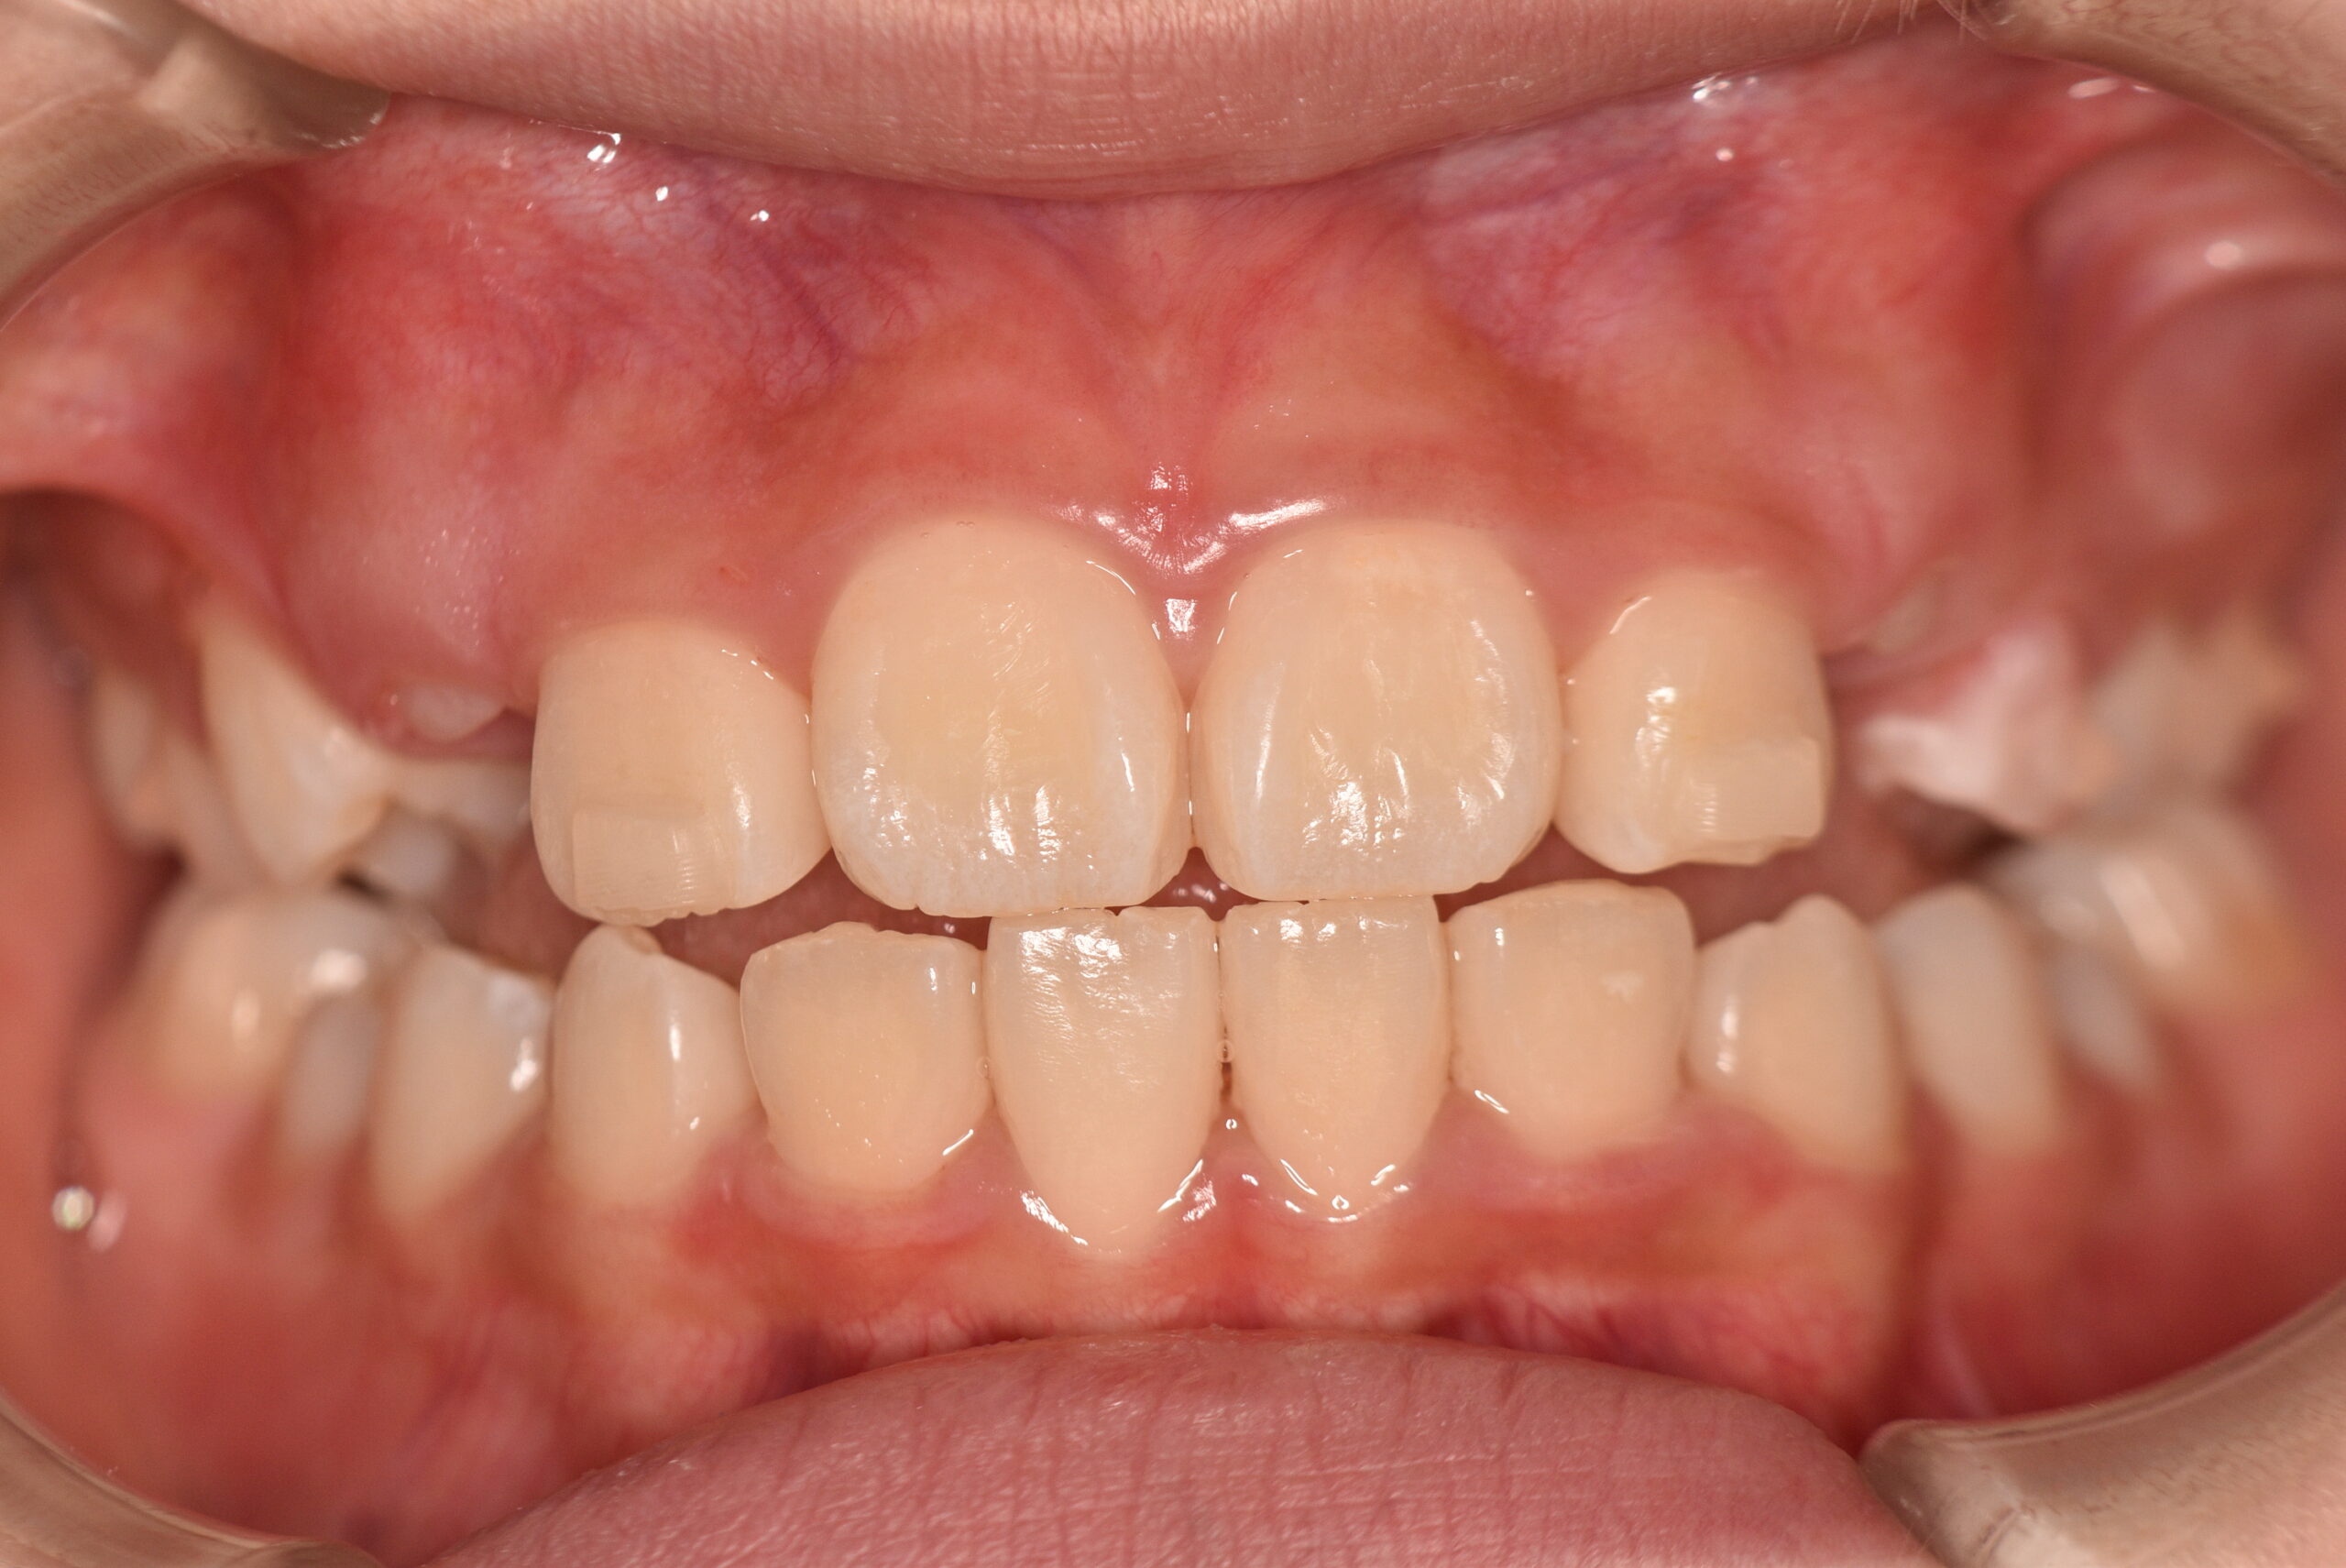

| 治療内容の詳細 | 初診時7歳の女児で、歯のがたつきを気にされ来院されました。 検査の結果、前歯部叢生を伴うアングルⅡ級不正咬合と診断しました。 治療としてはマウスピース矯正(インビザラインファースト)で配列を行い、上下顎の側方拡大と萌出スペースを確保しました。 治療期間は、1年でした。 今後、側方歯生え変わりまで経過観察を行います。 |